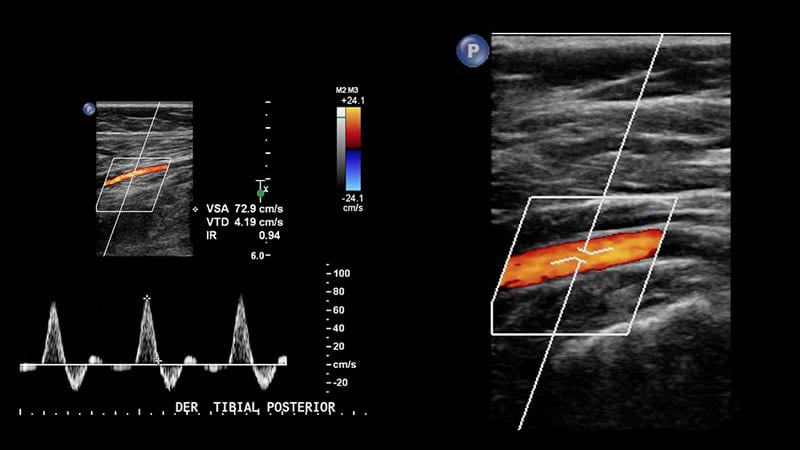

El estudio doppler venoso es hoy en día el método de elección para el estudio de las enfermedades de de las venas de los miembros inferiores. Permite evaluar varices y otras formas de insuficiencia venosa:

El estudio doppler arterial de MMII permite obtener información sobre el grado de enfermedad de las arterias de los MMII (pseudoaneurismas, fístulas arteriovenosas), seguimiento del tratamiento de revascularización, así como evaluación en la isquemia crónica o aguda).